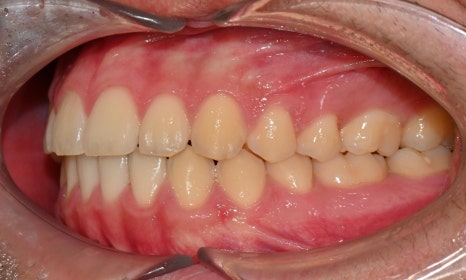

외관상으로는 아랫입술이 돌출되어 보이고 아래 치아가 좌측으로 치우치면서 치아 중심선(midline)이 맞지 않는 상태였습니다. 또한 환자는 어릴 적 넘어지면서 앞니가 깨졌던 외상 병력이 있었고, 그 영향으로 앞니 뿌리가 부분적으로 흡수된 상태였습니다.

2024.12. 초진 구내사진 - 연세정원치과

정밀 검진 결과, 하악 치열이 좌측으로 틀어져 있었고 그로 인해 위아래 치아 중심선이 일치하지 않았습니다. 아래 치열이 전체적으로 전방 위치하여 아래 입술 돌출이 더 도드라져 보이는 상태였습니다. 그리고 상악궁이 하악궁보다 좁아서 앞니 부위 일부 반대로 물리는 치아 교합도 관찰되었습니다. 특히 외상 치아의 경우, 교정력 적용시 추가적인 염증성 치근 흡수 위험이 존재하기 때문에, 치료 중 지속적인 관찰이 필수적인 상황이었습니다.

치료 시작 7개월 후 사진으로, 치아 배열 후 아래 우측에 미니스크류를 식립하여 치아 중심선을 개선하는 중으로, 교합과 치아 중심선이 많이 개선된 것을 확인할 수 있습니다.

약 1년 간의 교정 치료를 통해 어긋나 있던 치아 중심선이 자연스럽게 맞춰졌고, 중심선 비대칭이 개선 및 하악 아랫입술 돌출도 눈에 띄게 호전되었습니다. 무엇보다 치료 기간 동안 앞니의 치근 흡수는 추가적인 진행 없이 안정적으로 유지되었습니다.

돌출을 조금 더 개선하는 것을 추천했으나, 환자가 갑자기 군 입대를 하게 되어 현 상태로 치료를 마무리하기로 하였습니다. 치료 전후 치아 위아래 중심선이 일치하며 좌우 어금니 교합도 향상되었습니다. 하악 치열의 후방 이동으로 아래 입술의 돌출도도 많이 개선되었습니다. 멀리서도 믿고 내원해주고, 치료 기간 동안 성실히 협조해준 환자분께 감사드리며 앞으로도 건강한 치아로 군 생활 잘 마치길 응원합니다 :)